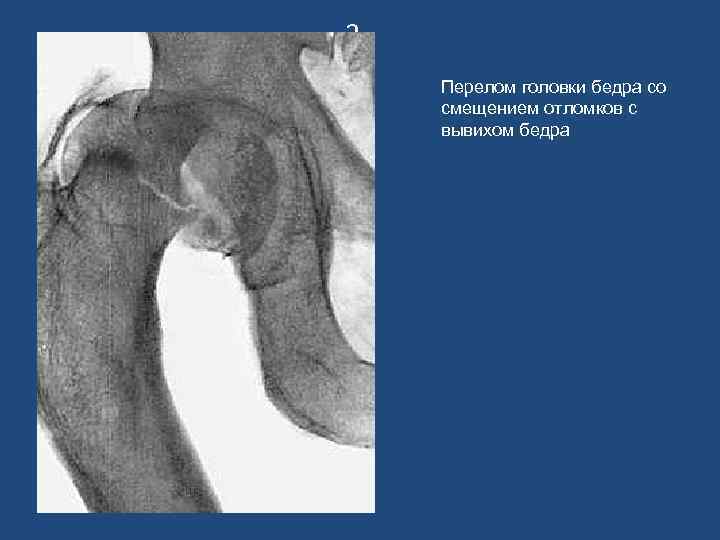

3 Перелом головки бедра со смещением отломков с вывихом бедра